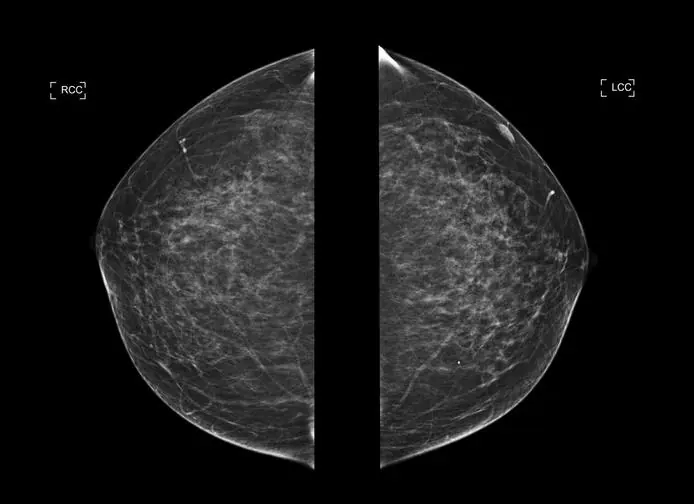

La mamografía digital 2D obtiene imágenes planas de la mama comprimida desde dos proyecciones estándar: cráneo-caudal (CC) y medio-lateral oblicua (MLO). Estas imágenes representan una suma de todo el tejido mamario en un solo plano. En contraste, la tomosíntesis realiza múltiples adquisiciones durante un movimiento en arco del tubo de rayos X, que generalmente oscila entre 15 y 50 grados.

Estas imágenes individuales, tomadas desde distintos ángulos, son procesadas mediante algoritmos avanzados que reconstruyen cortes delgados del tejido, con un grosor de 1 mm, lo que permite visualizar la mama en forma tridimensional.

En la mamografía 2D, las estructuras anatómicas se superponen en una única imagen, lo cual puede ocultar lesiones pequeñas o simular hallazgos patológicos. La tomosíntesis, al ofrecer cortes secuenciales, permite evaluar el tejido capa por capa. Esta visualización tridimensional proporciona un mayor contexto anatómico y facilita una diferenciación más clara entre tejido normal y alteraciones sospechosas.

Uno de los principales desafíos de la mamografía 2D es la superposición de tejido glandular, especialmente en pacientes con mamas densas, lo que puede enmascarar lesiones y dificultar la interpretación. La tomosíntesis disminuye considerablemente este efecto, ya que separa las estructuras superpuestas en cortes independientes, revelando anomalías que de otro modo podrían pasar desapercibidas.